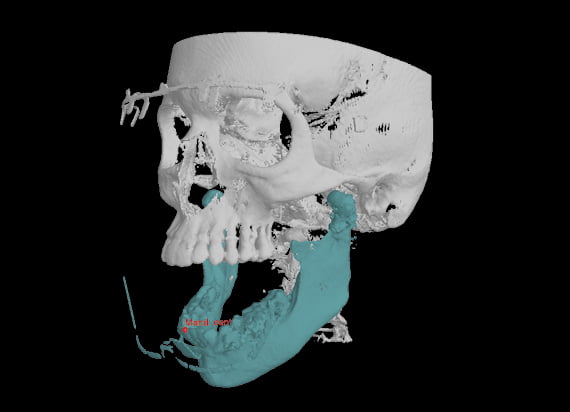

Tworzenie wirtualnych pacjentów

Jest to pierwszy system w branży, który łączy trzy różne typy danych 3D: skan CBCT, skan 3D twarzy i skan 3D modelu na jednym systemie rentgenowskim. To połączenie tworzy trójwymiarowego wirtualnego pacjenta w celu wizualizacji indywidualnych potrzeb klinicznych.